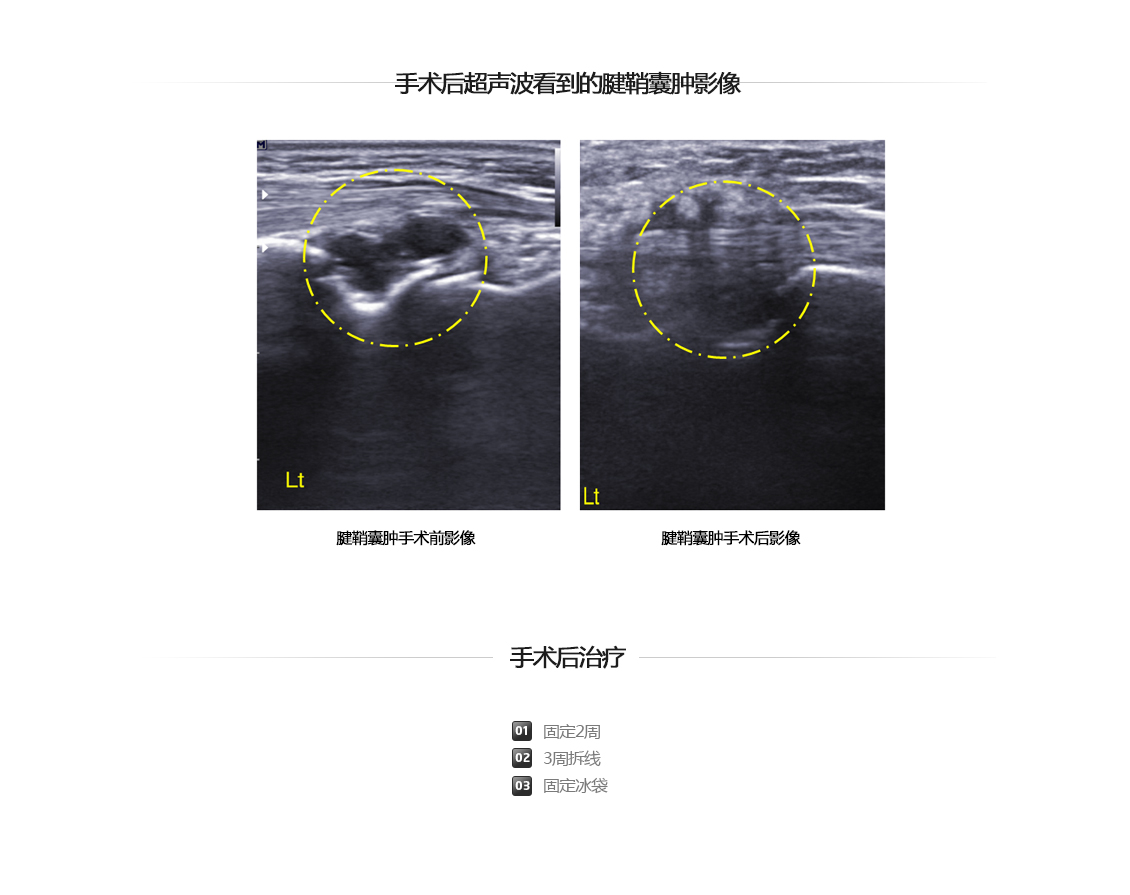

腱鞘囊肿